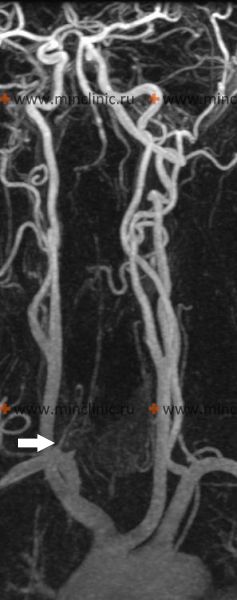

ვერტებრო-ბაზილარული სისტემისა და ტვინის უკანა არტერიის აუზის ათეროთრობოზული დაზიანება

მოგრძო ტვინისა და ხიდის საზღვარზე ხერხემლის ორი არტერია ერთდება და წარმოიქმნება ძირითადი არტერია. ძირითადი არტერია შემდეგ იყოფა ტვინის ორ უკანა არტერიად ფეხთაშორის ორმოში. ტვინის ამ მსხვილი უკანა არტერიებიდან გამოდის დიდი გრძელი და მოკლე შემომსალტავი ტოტები, რომლებიც სისხლით ამარაგებენ ნათხემს. მოგრძო ტვინს, ხიდს, შუა ტვინს, ჰიპოთალამუსს, თალამუსს, საფეთქლის წილის მედიალურ ნაწილებსა და თავის ტვინის კეფის წილს.

არსებობს ვარაუდები იმის შესახებ, თუ ხერხემლისა და ტვინის ძირითადი და უკანა არტერიების რომელი უბნები ზიანდება ათეროსკლეროტულად. ყველაზე ხშირად ათეროსკლეროზით ზიანდება ხერხემლის ორივე არტერიის საწყისი სეგმენტები და ძირითადი არტერიის პროქსიმალური (დასაწყისი) ნაწილი. გარდა ამისა, შეინიშნება ათეროსკლეროზული ფოლაქების წარმოქმნის ტენდენცია ხერხემლისა და ტვინის ძირითად და უკანა არტერიების საწყის განყოფილებებში.